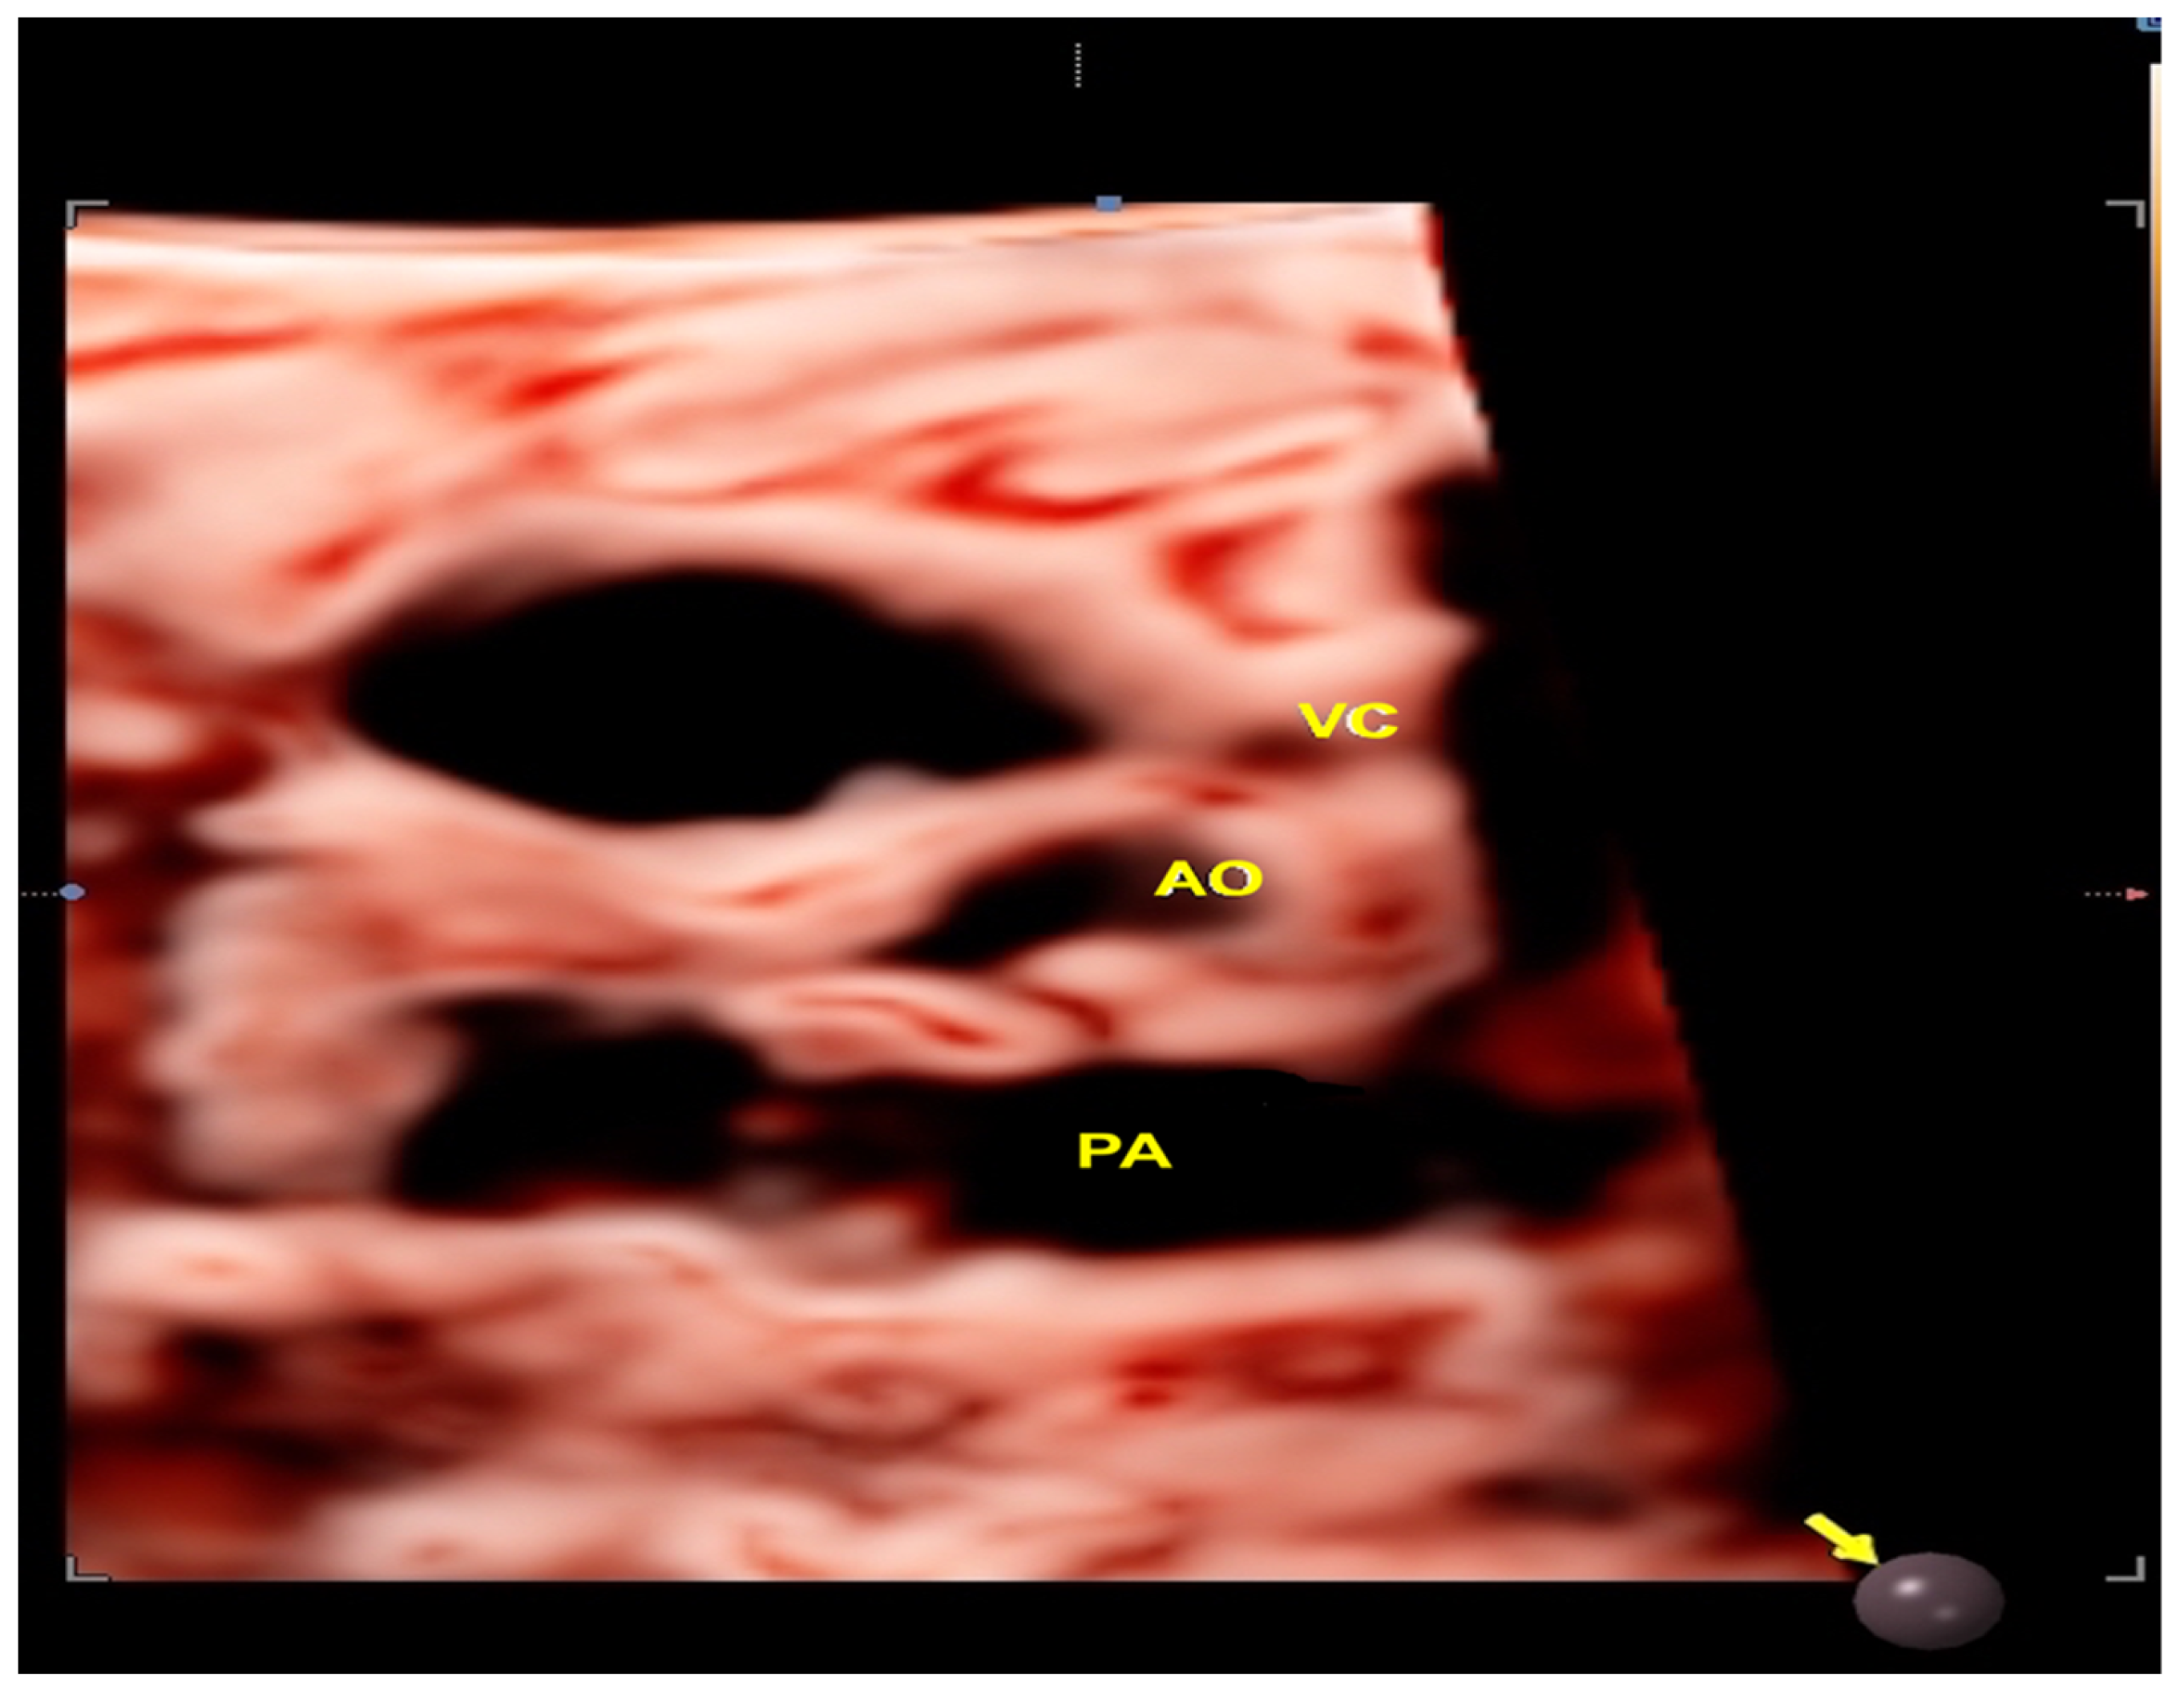

- Tie HX, Ma B, Zhang DC, Li TG. Prenatal diagnosis of fetal inferior vena cava malformation using HDlive flow combined with spatiotemporal image correlation. Echocardiography. 2022, 39, 685–690.

- Li TG, Ma B, Gao YH, Zhang RH, Li PL, Da ZQ. Prenatal diagnosis of total anomalous pulmonary venous connection using 2D and HDlive flow combined with spatiotemporal image correlation. Echocardiography. 2022, 39, 1269–1275.